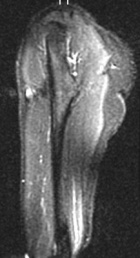

29 year old WF with swelling right deltoid of five months duration, no history of trauma, also c/o tingling in thumb and all fingers

Zoom image: Radiological image Radiological image.